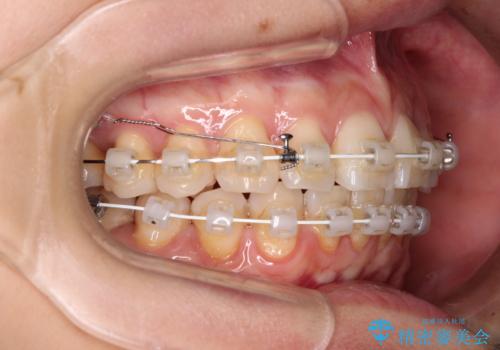

- 矯正装置

- 審美装置

- 奥歯の咬み合わせと、上下前歯の隙間を気にして来院された患者様です。

上顎の歯列全体が、下顎歯列に対して前方に位置しており、その影響で上顎前歯がやや前方に突出している状態でした。

横顔の印象から、抜歯をして積極的に口元を引っ込める必要はなかったため、アンカースクリューを用いて上顎歯列全体を後方に移動させることとしました。

奥歯の咬み合わせは理想的な状態に改善され、その結果として上下歯列もバランスの良い位置に収めることができました。

若干ではあるものの上顎前歯を内側に移動させることができ、以前よりも口が閉じやすいと感じるようになりました。